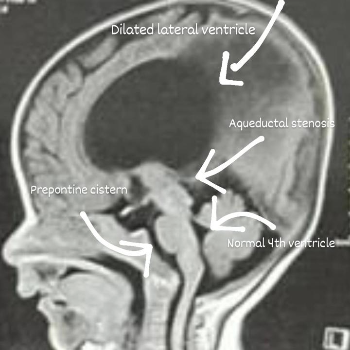

Dr. Rege’s clinic is more than just a medical facility; it's a sanctuary where science and compassion intersect. Pediatric neurosurgery, a specialized field, is designed to tackle the intricate challenges of neurological conditions in children. These conditions can range from brain tumors and epilepsy to congenital spine disorders. Each case is unique, demanding a personalized approach that considers the delicate nature of a child's developing brain and spine.